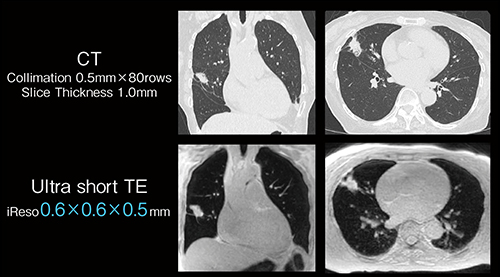

UTE-MRIは、通常よりも極端に短いecho time(TE)によって従来の撮像法では描出が難しかったT2*値の短い組織を観察する撮像法である。肺は、空気を多く含みプロトン密度が低く、また組織と空気の境界で起こる磁化率効果で信号減衰が速いためMRIでの画像化が困難だった。UTE-MRIでは100μs以下のTEで高分解能MRIが撮像でき、大野臨床教授は胸部領域で肺実質の血管や気管支などの構造や疾患の診断が可能なことを報告してきた2)。また、UTE-MRIは動きの影響を受けづらいことから自由呼吸下での撮像が可能になる。大野臨床教授は、「図1では、右中葉に長径19mm大のpleural indentation、notchおよびspiculaを伴った結節を認め、肺腺癌を疑います。UTE-MRIは、被ばくなしに薄層CT(Thin-section CT: TSCT)と同等の描出能があり、肺実質の評価を含めた各種の肺疾患の診断が可能です。さらに、MRIでは、拡散強調画像や造影、CESTなどさまざまな情報を合わせた、multi parametricな診断の可能性が広がります」と述べる。

図1 UTE(Ultra short TE)